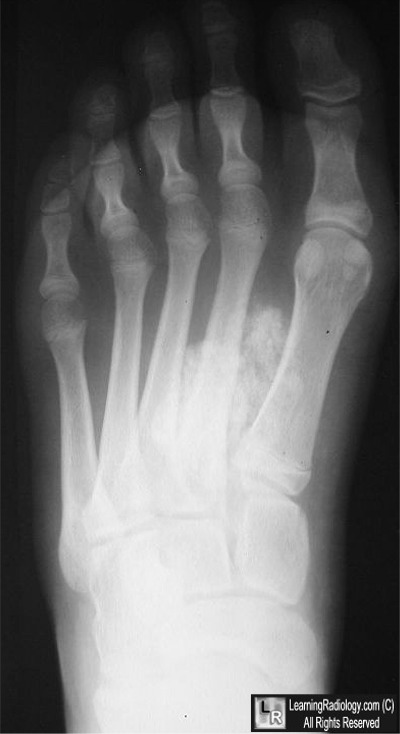

Case of the Week 555

What is the most likely diagnosis?

• 18 year-old with slow-growing mass in foot

Frontal radiograph of the foot

4. Synovial Sarcoma

Synovial Sarcoma

General Considerations

• Middle-aged and older adults

• Most frequent presentation: painful

swelling of the knee

• Predisposition for lower extremity

• It is a malignancy

• Can occur at any age

• Usually third and fourth decades

• Usually are extra-articular